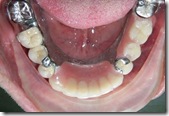

患者A先生

上顎 正面 下顎

患者B小姐

以上兩位患者口內狀況非常複雜,要制定一個好的治療計畫,

不只要考慮到患者的牙齒條件,

還要顧及患者意願、時間、金錢、評估可獲得的結果等等。

所以像這類型的Case 醫師通常在初步的溝通後會先做出一兩個不同的治療計畫,

再和患者解釋,了解患者接受程度。